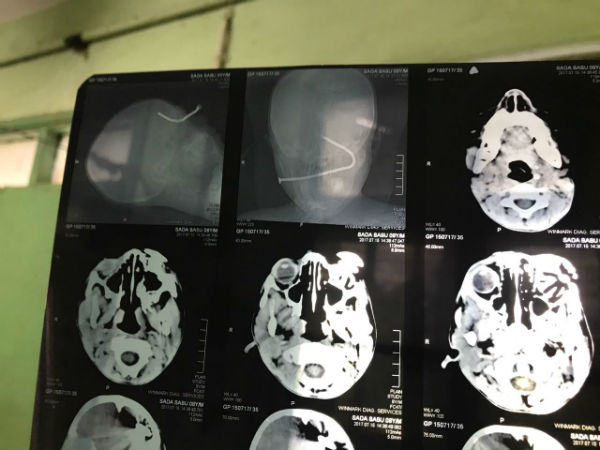

চোখে পেরেক ঢোকা অবস্থাতেই একের পর এক সরকারি হাসপাতালর দরজায় ঘুরতে হল ছোট্ট করিম মোল্লাকে। প্রায় ৭ ঘণ্টা পর অবশেষে তাকে ভর্তি করিয়ে অস্ত্রোপচার হল এনআরএস হাসপাতালে। আপাতত বিপন্মুক্ত হলেও মস্তিষ্কের ক্ষতি নিয়ে চিন্তায় চিকিৎসকেরা। এই ঘটনায় উদ্বেগপ্রকাশ করে রবিবার বারবার করিমের খোঁজ নিলেন খোদ মুখ্যমন্ত্রী।

শনিবার দক্ষিণ ২৪ পরগনার কুমিরমারির বাসিন্দা করিম মোল্লা বাঁশের মাচা থেকে পড়ে যায়। বাঁশের মাচায় থাকা একটি বড় পেরেক তার চোখে গেঁথে যায়। তড়িঘড়ি তাকে ক্যানিং মহকুমা হাসপাতালে নিয়ে যাওয়া হলে উপযুক্ত পরিকাঠামোর অভাবে তাকে কলকাতায় রেফার করে দেওয়া হয়। কিন্তু কলকাতায় তার জন্য কী হয়রানি অপেক্ষা করছিল তা হয়ত স্বপ্নেও ভাবেনি করিম। ন্যাশনাল মেডিক্যাল তাকে ফেরানোর পর এসএসকেএম হাসপাতালও তাকে বাঙুল হাসপাতালে রেফার করে। সেখানেও গিয়েও হতাশ হতে হয়েছে করিমের পরিবারকে। বাঙুর থেকে কলকাতা মেডিক্যাল কলেজে পাঠানোর পর সেখানে ভর্তি নেওয়া হয়নি করিমকে। অবশেষে এনআরএস হাসপাতালে ঠাঁই হয় তার। কিন্তু ততক্ষণে সাত ঘন্টারও বেশি সময় পেরিয়ে গিয়েছে। এরপর সংবাদমাধ্যমের উদ্যোগে করিমের চোখের অস্ত্রোপচারের তোড়জোর শুরু হয়। রাতেই অস্ত্রোপচার করে চোখ থেকে পেরেকটি বের করেন চিকিৎসকেরা।

অপরদিকে রবিবার করিমের অবস্থা অনেকটাই স্থিতিশীল। তবে তার দৃষ্টিশক্তি থাকবে কিনা সেবিষয়ে এখনই কিছু বলতে পারছেন না চিকিৎসকরা। আপাতত পেরেক ঢুকে তার মস্তিষ্কে যে গভীর ক্ষত তৈরি হয়েছে, তা নিয়েই বেশি উদ্বিগ্ন চিকিৎসকেরা।